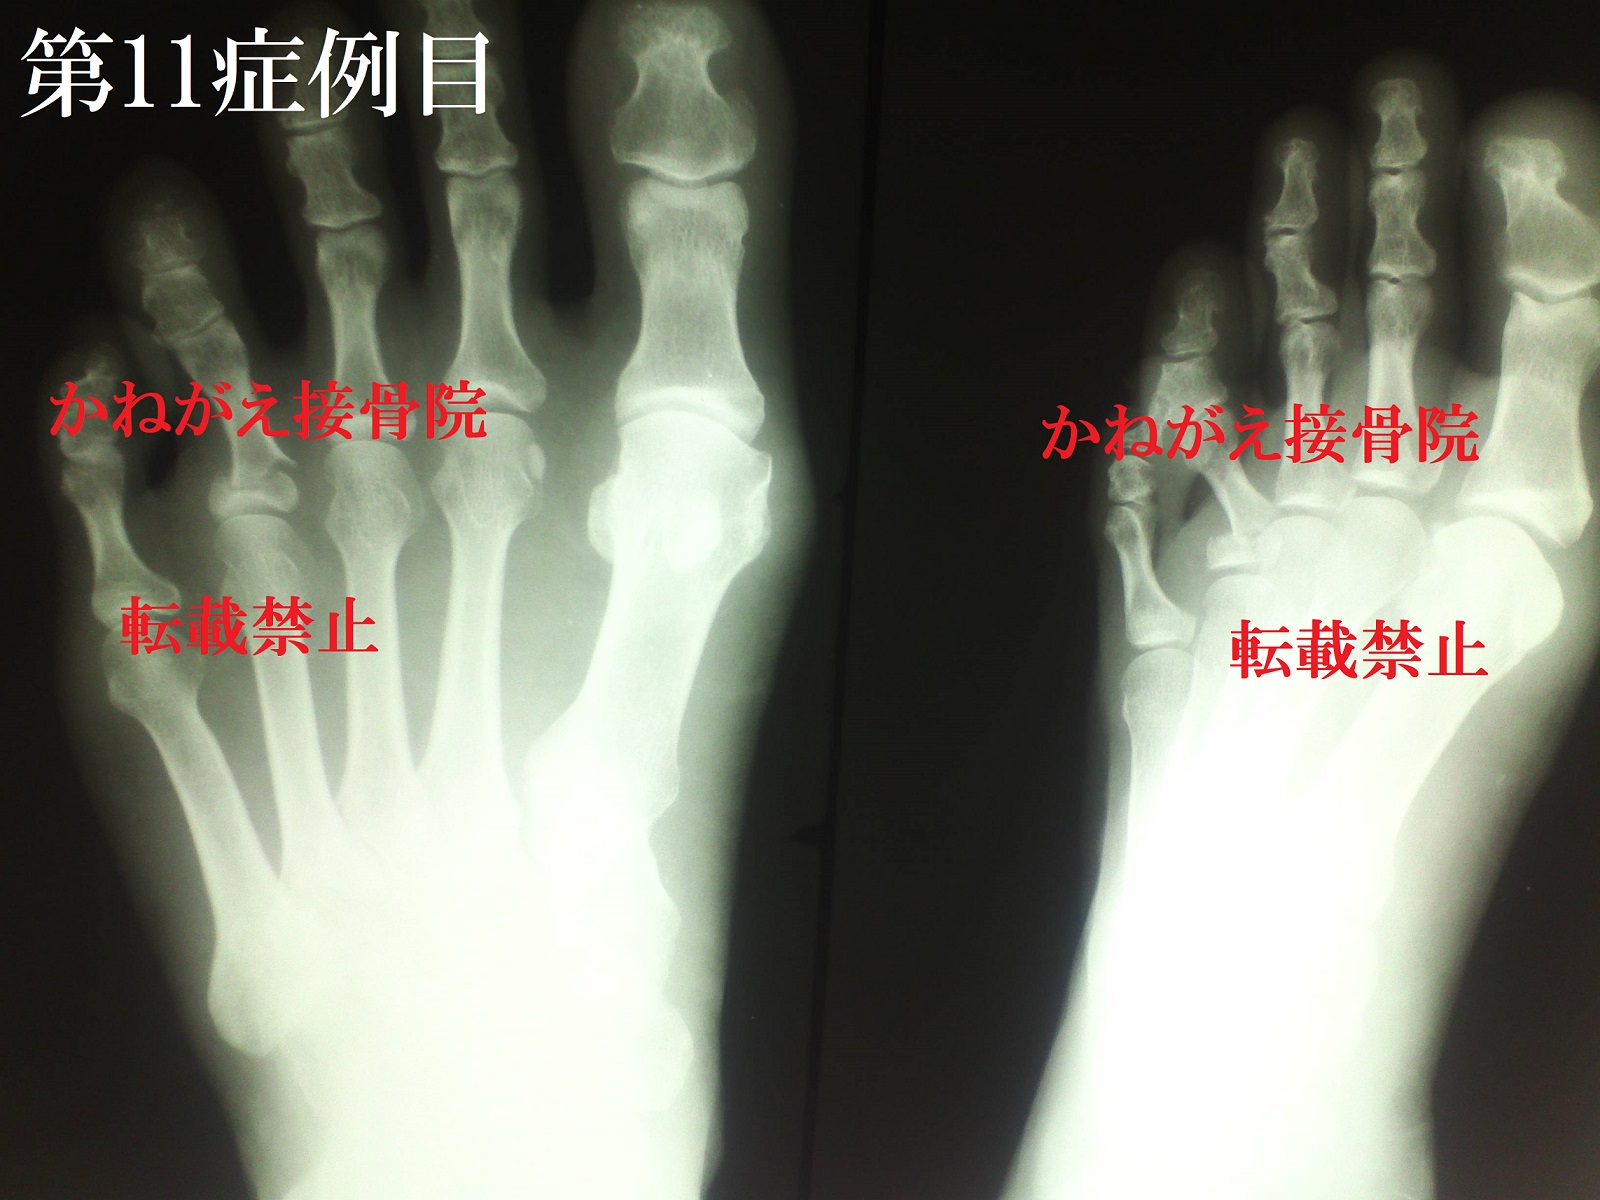

症例11

当時51歳 女性

左第4趾基節骨骨折

結果から言うと「Repo perfect」で

した。

転位が顕著な症例なので、写真をみれば一目瞭然

でしっかり戻っているのがわかるかと思います。

今回の症例は、

背屈転位(足の甲側に曲がってしまった状態)

外転転位(指の場合は、小指側に曲がってしまっ

た状態)

底側転位(足の裏側にズレた状態)

内側転位(足の場合は母趾側にズレた状態)

側方転位は「骨折して一方の骨片が骨長軸上より

側方に転位したもの」という定義ですが、今回の

症例は折れた足趾が位置を留めたまま左斜め上方

向に回転している状態なんです。

その為長軸上からみて底側・内側に転位というこ

とになります。